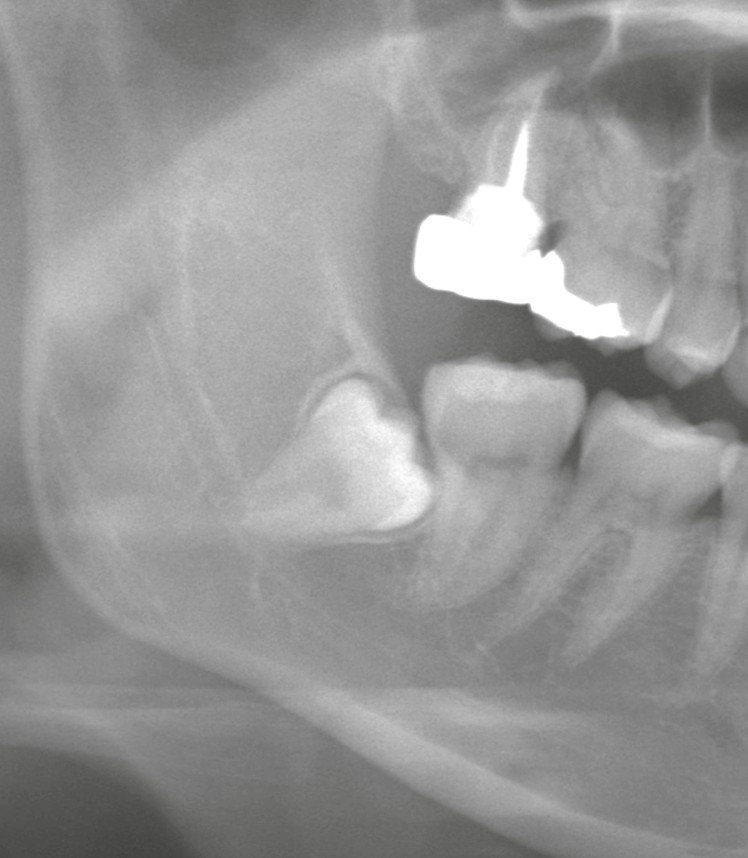

オヤアゴで行われる抜歯の多くは「通常抜歯」ではありません

当院に紹介される親知らずは、

* 完全埋伏・水平埋伏

* 下歯槽神経や上顎洞への近接

* 歯根形態が複雑

* 過去に抜歯を断られたケース

といった、難易度の高い症例が中心です。